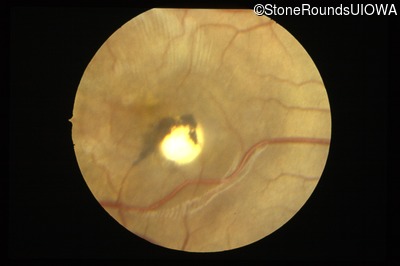

Fundus Photography - Right - 20/40 -1

Exemplar

Fundus Photography - Left - 20/20 -2